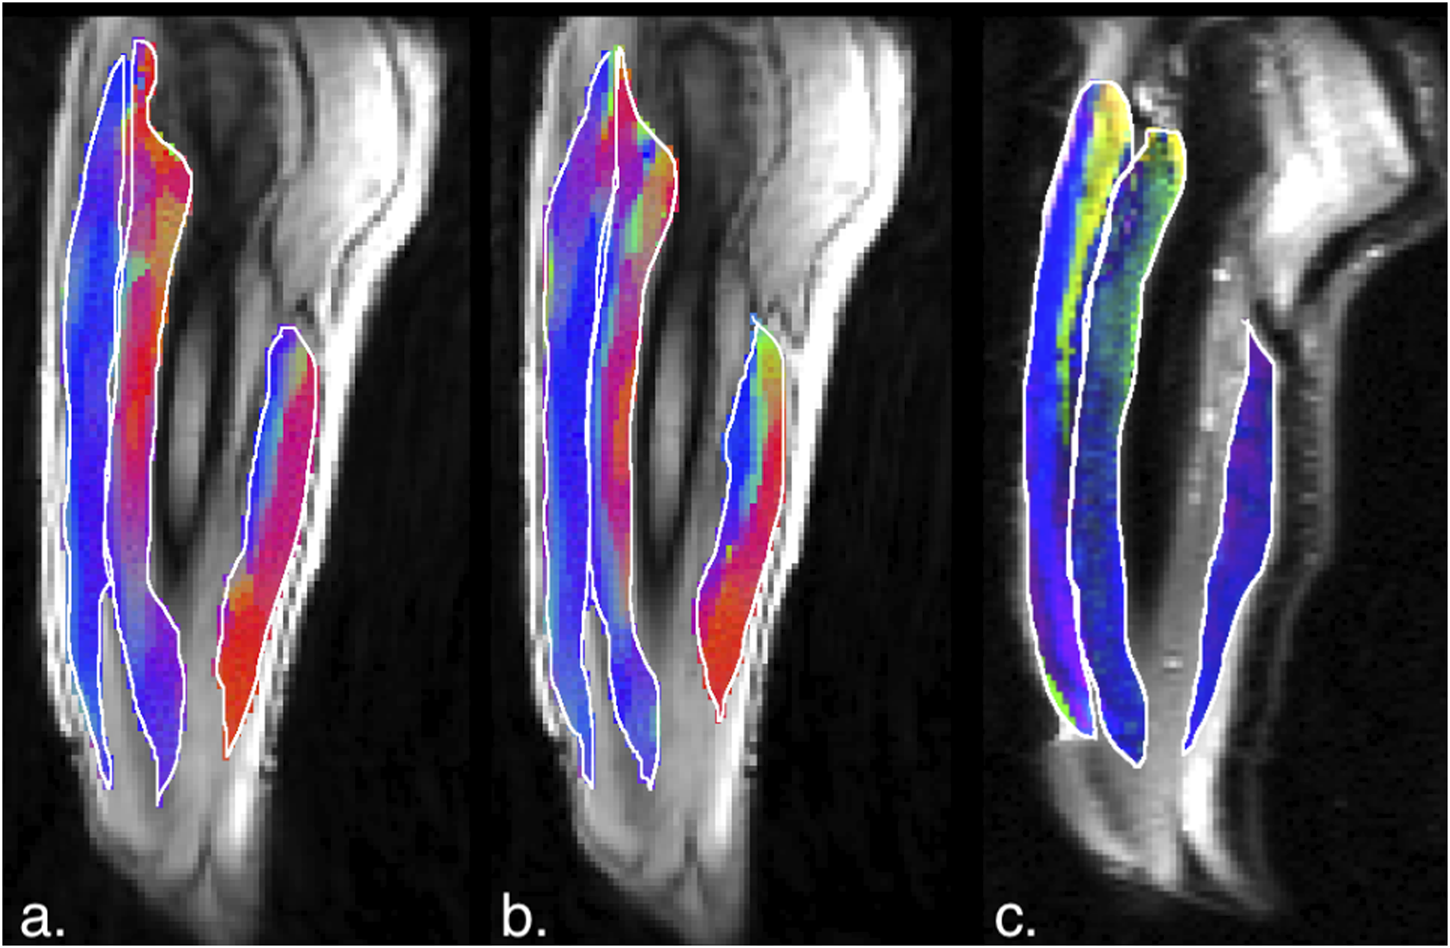

Figures 5, 6 are temporal plots of muscle kinematics extracted from ROIs placed in the VM muscle and LBF muscles respectively; plots are shown for one subject during isometric contraction at 30%MVC. Of note is that the velocity in the VM (quadriceps) and LBF (hamstring) are opposite in sign indicating the agonist-antagonist activation pattern. Figure 7a is the colormap derived from the eigenvector corresponding to the negative eigenvalue and is shown for one slice at the peak of the contraction cycle at 45% MVC; the colormaps are shown inside the contours of three muscles manually outlined in the magnitude image: from left to right in each image, the contours are VL, VI and LBF. Figure 7b is the colormap from the same slice and temporal frame (as Figure 7a) at 30% MVC. The colormap of the lead eigenvector of the diffusion tensor imaging (DTI) in a matching slice is shown in Figure 7c. It should be noted that the DTI suffers from susceptibility induced artifacts arising from the fact that these images were acquired with a large FOV in the sagittal plane to cover the length of the thigh. The muscles were manually contoured independently on the baseline image of the DTI and the colormaps are shown inside the contours of VL, VI and LBF muscles. The DTI colormap confirms that the fibers in the thigh are aligned predominantly in the superior-inferior direction. Figures 8a–c shows images arranged similarly to Figures 7a–c for the same subject but at a different anatomical location. The manual contours of the muscles in Figure 8 refer to the following from left to right: RF, VI and ST/SM muscles. Note the quadriceps muscles are labeled as ST/SM as the contoured muscle is possibly a mixture of both.

Figure 7. (a) Magnitude image with colormaps shown within manually outlined contours of the vastus lateralis, vastus intermedius and the biceps femoris long head muscles (from left to right). The colormap shows the eigenvector direction corresponding to the negative eigenvalue at the temporal frame at the peak of contraction at 45% MVC. The following color mapping scheme is used: red hue (x-component, Medial-Lateral), green hue (y-component, Anterior-Posterior), blue hue (z-component, Superior-Inferior). (b) Image similar to that show in (a) for the same anatomical location at 30%MVC effort. (c) Colormap of the lead eigenvector of the diffusion tensor imaging (DTI) at the location of the dynamic image with the same three muscles manually outlined. This colormap shows the direction of the muscle fibers.

The agonist/antagonist behavior can be seen in the temporal plots of the velocity where the velocity is positive in the quadriceps muscles in the contraction phase while it is negative in the hamstrings; the latter finding indicates that when the quadriceps are contracting, the hamstrings are lengthening (coactivation). It should be noted that the incompressibility of muscle tissue combined with transverse asymmetry of muscle deformation leads to a negative eigenvalue and a positive eigenvalue with nearly equal magnitudes at each voxel. When the muscle is contracting during the dynamic cycle, the direction of the negative eigenvalue (contraction) will be approximately along the fiber direction and the direction of the positive eigenvalue will be perpendicular to the fiber, i.e., in the fiber cross-section. The opposing action of the hamstrings to that of the quadriceps is seen in the colormaps of the eigenvectors corresponding to the compressive (negative) strain in the contraction phase of the dynamic cycle. The colormap of the negative strain eigenvector at contraction shows the VL and RF (quadriceps) muscles have a predominantly blue hue indicating the strain eigenvector is along the superior- inferior direction while the hamstring muscle (LBF and ST/SM) have a predominantly red hue (albeit with some heterogeneity) indicating the strain eigenvector is along the medial-lateral direction. This indicates that positive strain exists along the muscle fibers of the hamstrings (lengthening) during the contraction cycle when the quadriceps muscles are contracting. The VI muscle has a more heterogenous colormap at both anatomical locations. However, as visualized in the diffusion colormap, the VI fiber orientation has a blue to blue-green hue as one traverses from distal to proximal. This, combined with the fact that fibers are known to rotate on isometric contraction could potentially cause the strain colormaps to reflect the rotated fiber direction at the peak and not at the start of the contraction (time point at which the DTI was acquired). The extent of fiber rotation is also likely to be dependent on the muscle. Future work will be focused on reorientating the DTI derived eigenvectors using the displacements derived from the dynamic imaging to compute the fiber orientation at the peak of the contraction. It is acknowledged that the strain colormaps are noisy; this arises from the fact that noise is amplified when spatial gradients of displacements are computed to extract strain. Anisotropic diffusion filtering of the phase images as well as the colormaps served to reduce some of the noise; future work will be focused on further reducing noise. However, the fact that the colormap of the strain eigenvector is similar for 30% and 45% MVC indicates that these are consistent and robust determination of the orientation.